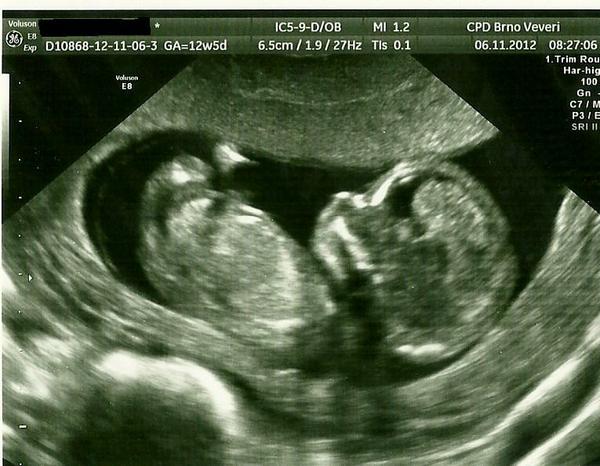

@blana12 Tak jsem dnes byla se sestrou v Prenatalu a viděla jsem fotečku s podobně úžasným zázrakem, jaký máš ty 😀 😀 🙂 !!! Termín jí posunuli na 19.5. a naštěstí je všechno v pořádku. Tak jsem ráda a jdu vymýšlet, jako ta nejhodnější tetička, jaký dárek miminku naložím - teda Ježíšek - pod stromeček 😀 😉 🙂 .